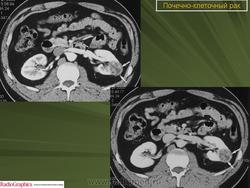

Рак почки.